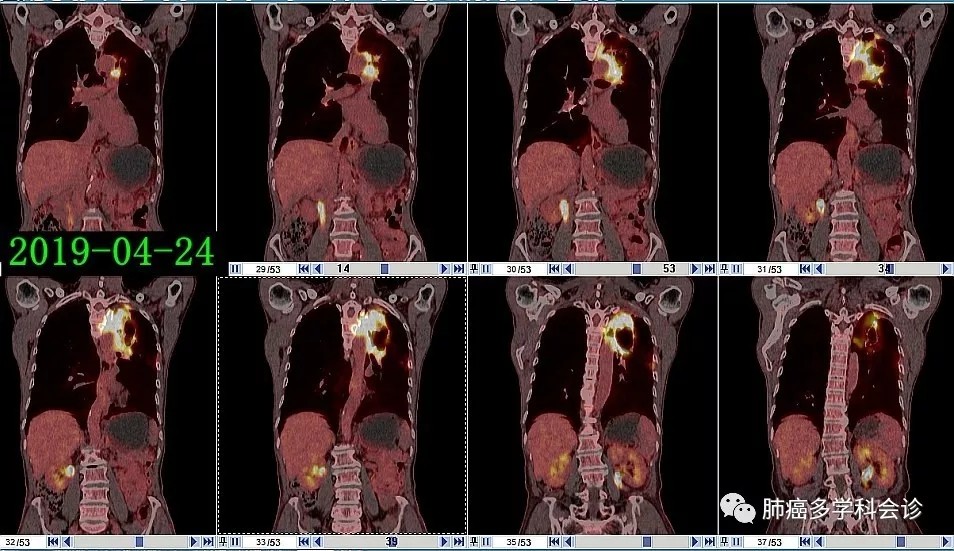

患者安ZHJ,男,82岁。2018-11-27在体检时发现左上肺占位,未再检查和治疗。2019-04-14复查CT:左肺上叶占位,右肺上叶钙化灶,左侧胸腔积液,双侧胸膜增厚并右侧钙化。从不吸烟。

PET CT 图像和报告如下:

1.webp.jpg2.webp.jpg3.webp.jpg因患者年迈年弱,治疗心切,放弃了参加“沃利替尼”新药临床试验的机会,口服“克唑替尼”治疗,1个月后肿瘤明显退缩: